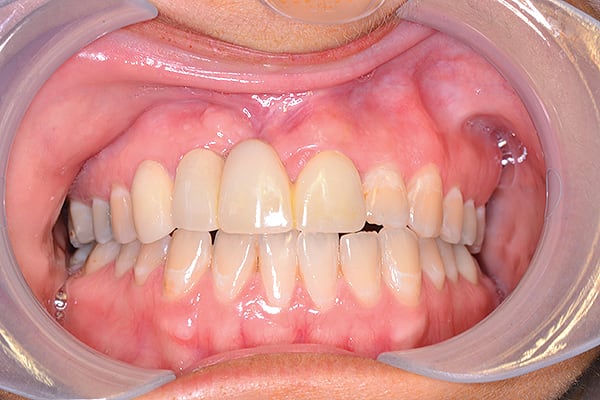

Figure 18

Figure 18 Patient’s smile at 1.5-year follow-up.